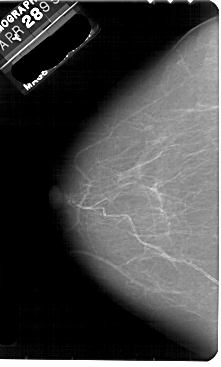

A_1881_1.LEFT_CC

LEFT_CC LINES 5491 PIXELS_PER_LINE 3301 BITS_PER_PIXEL 12 RESOLUTION 43.5 NON_OVERLAY

FILE: A_1881_1.RIGHT_CC.OVERLAY

TOTAL_ABNORMALITIES 1

ABNORMALITY 1

LESION_TYPE MASS SHAPE LOBULATED MARGINS ILL_DEFINED

ASSESSMENT 4

SUBTLETY 4

PATHOLOGY BENIGN

TOTAL_OUTLINES 1

BOUNDARY